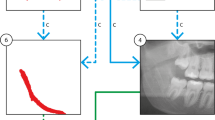

Overall architecture of the distance-aware network

We designed a distance-aware network consisting of cascaded stages of segmentation and classification (Fig. 2). In the segmentation stage, a U-Net of DenseNet121 [36] backbone with the input of 2D axial images (S-Net) was used for multiclass segmentation of the M3 and the MC, simultaneously. In the classification stage, a 3D distance-aware classification network with input of multiple volumes (C-Net) was designed for classifying the buccal-lingual relationship of the M3 and the MC by learning their 3D anatomical and geometrical information.

The 3D distance-aware network consisting of segmentation and classification stages for classifying the positional relationship between the third molar and the mandibular canal. In the segmentation stage, the third molar and the mandibular canal were simultaneously segmented using Dense121 U-Net. In the classification stage, the 3D distance-aware network with inputs of CBCT volume and the distance map classified the buccal-lingual positional relationship between the third molar and the mandibular canal

For multiclass segmentation of the M3 and the MC, we used a pre-trained DenseNet121 backbone as the encoder of the U-Net, which consisted of multiple densely connected layers and transition layers to improve feature propagation and alleviate the vanishing gradient problem (Fig. 2). The decoder was composed of a five-level structure where each level consisted of a 2 × 2 up-sampling layer, a skip connection, and two convolutional blocks. Each convolutional block consisted of a 3 × 3 convolutional filter, a batch-normalization layer, and a rectified linear unit (ReLU) activation function. The SoftMax activation function was applied to the last activation layer for outputting multiclass segmentation of both the M3 and the MC. Several U-shaped networks such as SegNet [37], simple U-Net [38], and Attention U-Net [39] were also used as segmentation networks for performance comparison.

For classification of the positional relationship between the M3 and the MC, we designed a 3D distance-aware network (C-Net) consisting of a five-level structure where each level consisted of a 3 × 3 × 3 convolutional layer, a batch-normalization layer, the ReLU activation function, and a 2 × 2 × 2 max-pooling layer (Fig. 2). The original CBCT volume, binary segmentation mask from predictions, and corresponding SDM were used as multichannel inputs for the C-Net. The input volumes were centered at the point where the M3 and the MC were closest. In the output layer, the class probability for the relative buccal-lingual position of the MC was calculated using the SoftMax activation function following the global average pooling layer and the dense layer. The predictions by the segmentation networks of SegNet, simple U-Net, Attention U-Net, and Dense U-Net were also used as the input of the classification network for performance comparison.

Signed distance map (SDM) for positional information

In the classification process, the network learned the 3D anatomical and geometrical information from the multichannel volume inputs simultaneously. The SDM calculated from the mask result of the segmentation prediction was used as an input for learning the geometrical information, while the original CBCT image was used for learning the 3D anatomical information (Fig. 3). The geometric SDM between the M3 and the MC from the segmentation prediction was calculated as the signed distance transform (SDT) [40]. The SDT was defined as the Euclidean distance from the nearest background point: